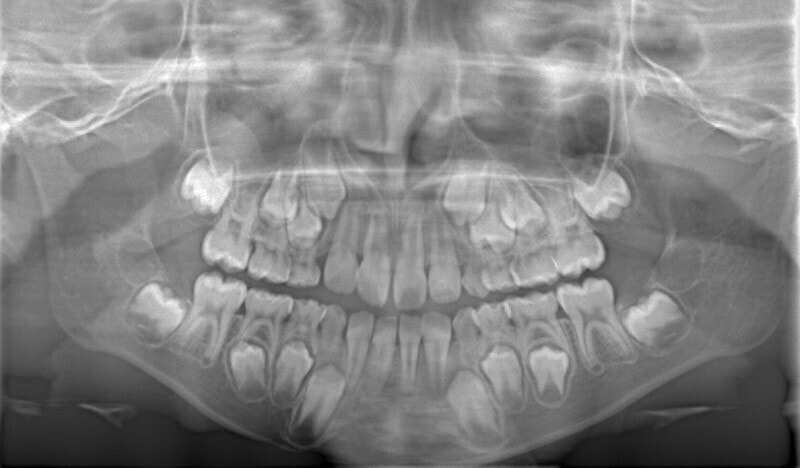

治療前

診断:初診時では右上3番の萌えるスペースがほとんどなく、顔と上顎と下顎の正中に対して、上顎前歯の正中が右にずれこんでいます。その影響で右上2番が右下乳歯Cと反対咬合になっています。放置すると、右上3番が埋伏歯になり、下顎の成長が左方向に流れるので、成長とともに顔面の非対称が増悪されることが予測されます。

右上乳犬歯が既に脱落しており、右上犬歯の萌出スペースがゼロになっています。